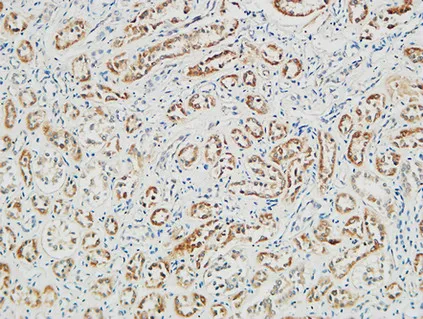

PGD Rabbit Polyclonal Antibody

Cat: APRab16027

Size1:50μl Price1:$118

Size2:100μl Price2:$220

Size3:500μl Price3:$980